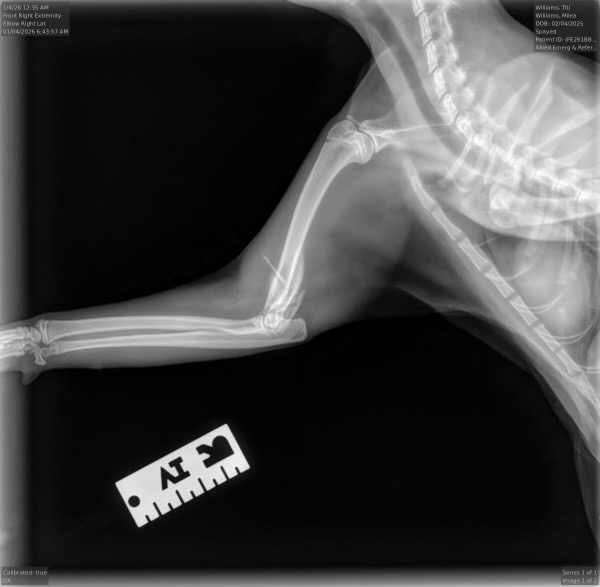

Ti Ti is our sweet 11-month-old kitten, and she means everything to my daughter. Recently, Ti Ti suffered a serious injury—she broke the humerus bone in her front leg. We were devastated to learn that surgery to repair the bone would require a specialist and is far beyond what we can afford. Because of this, the only option left is to have her leg amputated, which comes with its own challenges and costs.